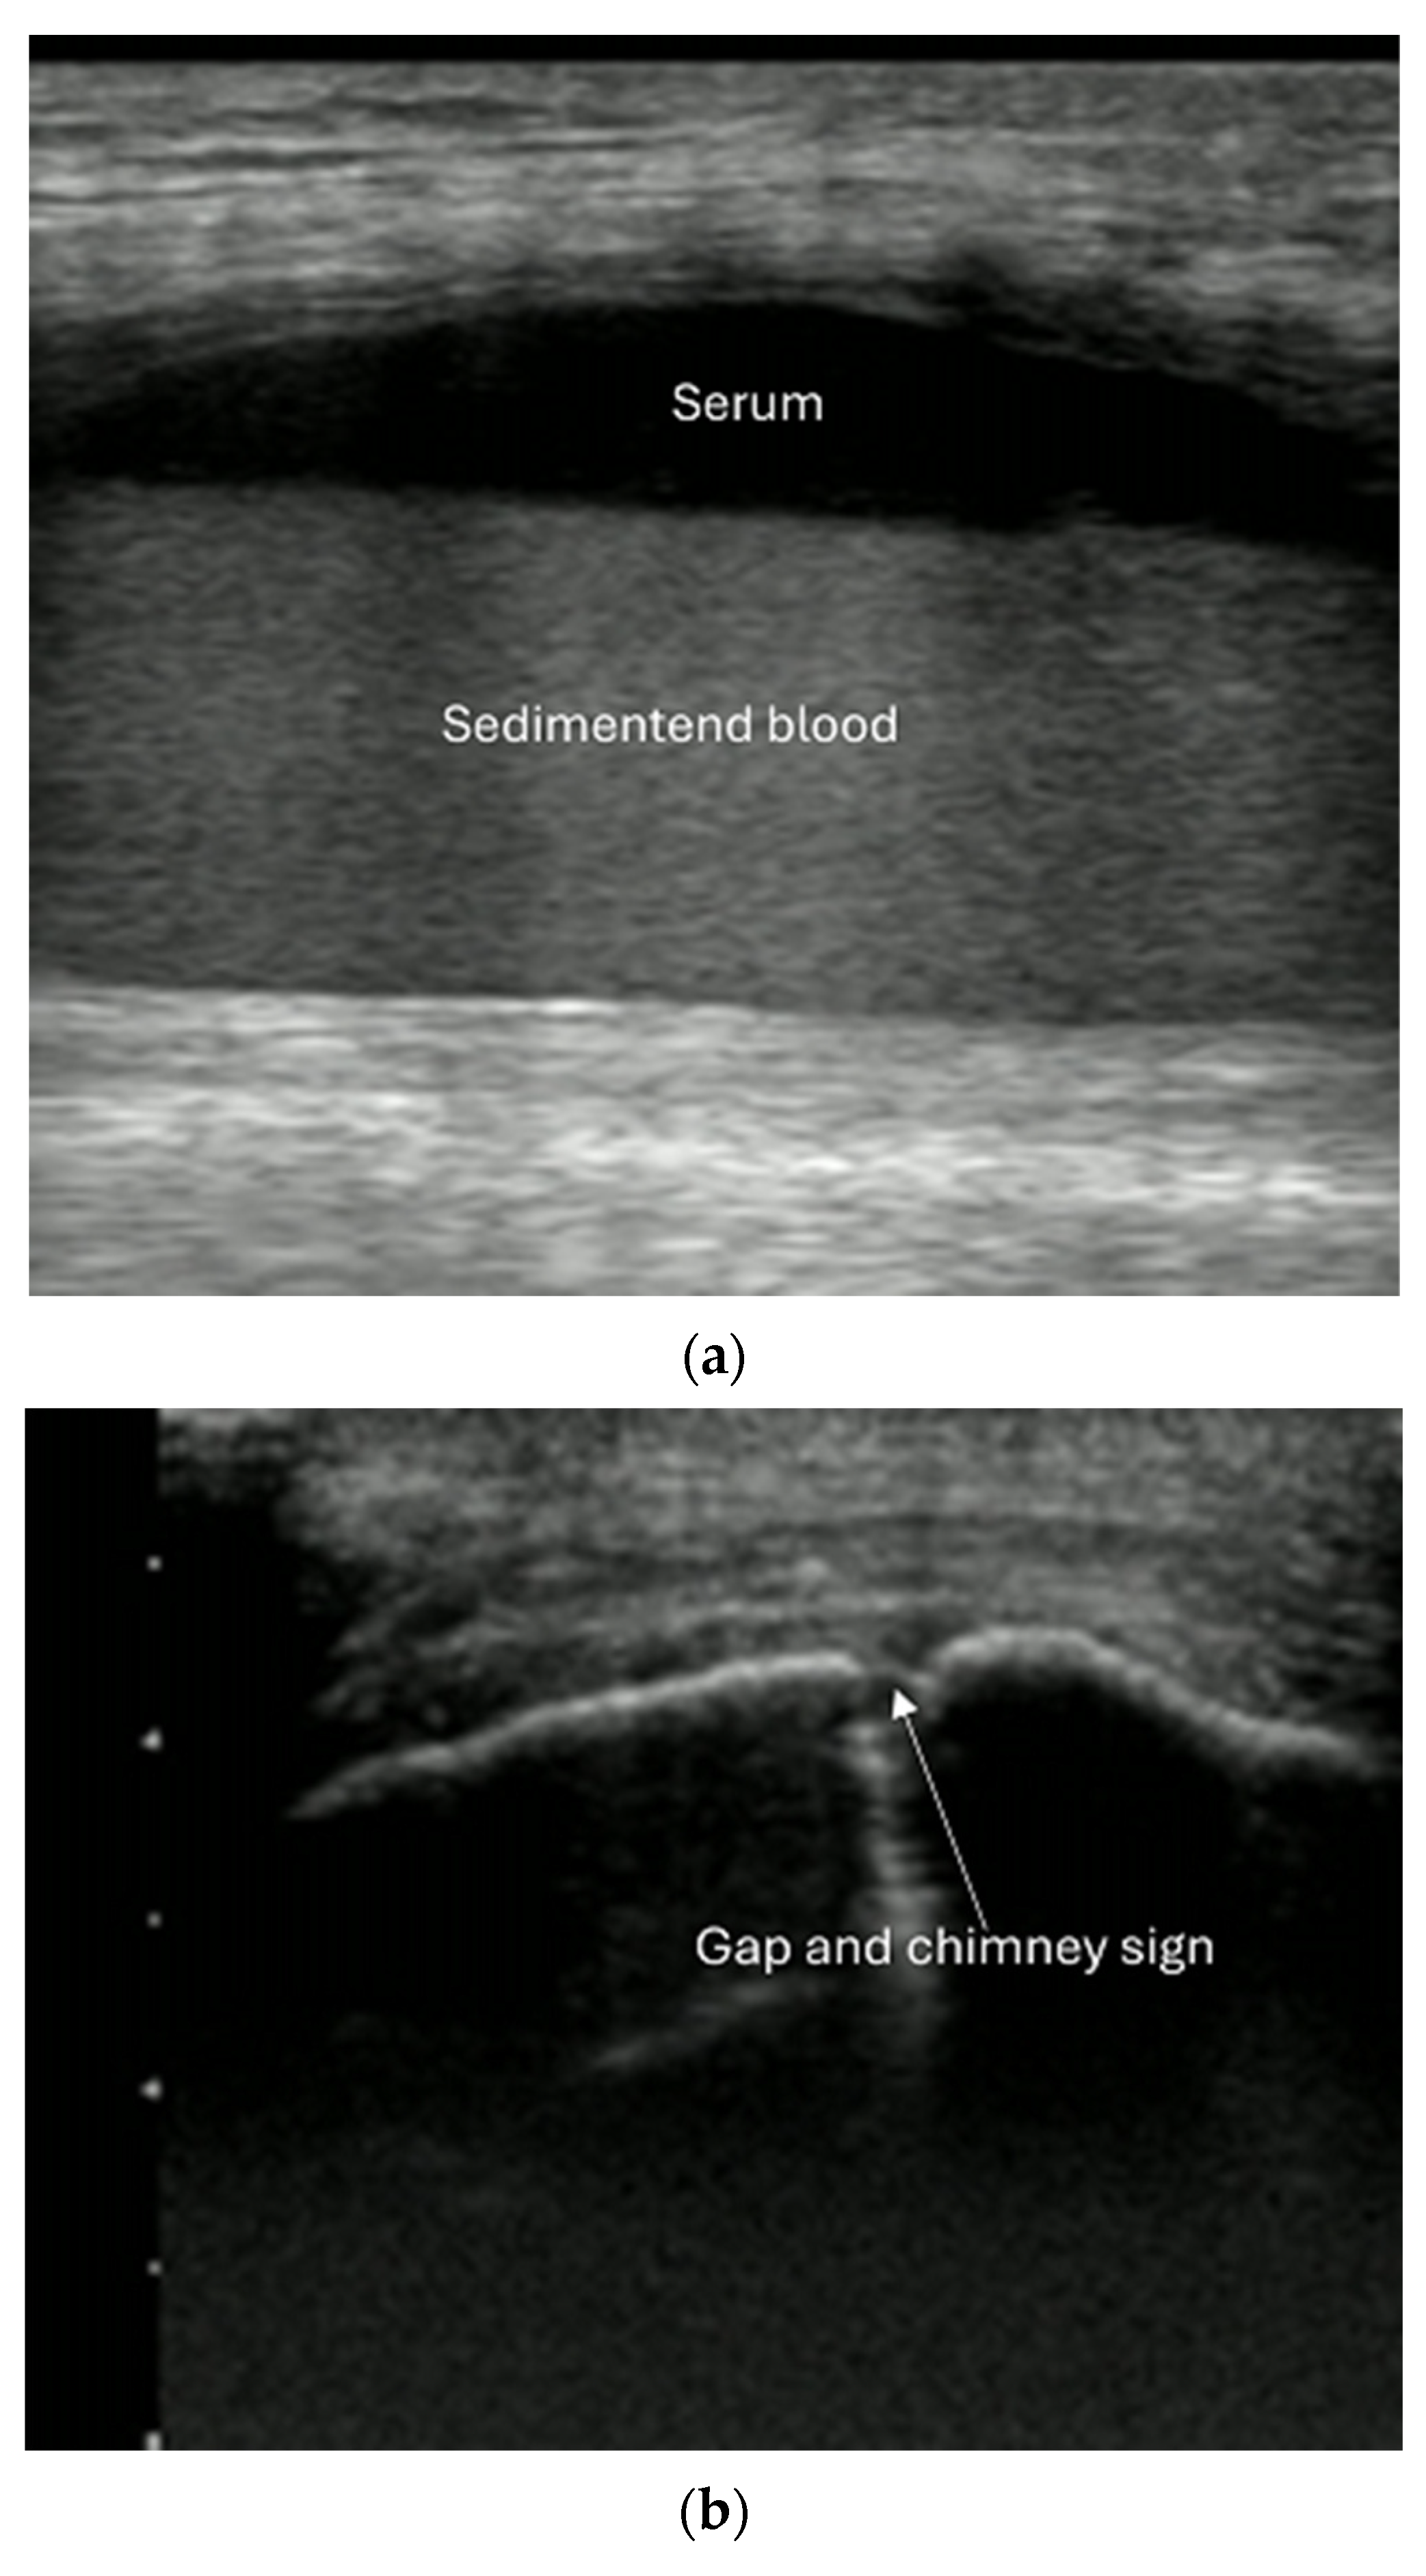

- Irregularity, interruption, or gaps in the cortical line: the cortical bone normally appears as a continuous, bright echogenic line, which is interrupted or irregular in the presence of a fracture.

- Reverberation artifacts within or adjacent to the fracture gap (also known as the “chimney sign”): these repetitive echoes are caused by ultrasound waves reflecting off the fracture surfaces.

- Local hematoma or soft tissue edema: fluid collections or increased echogenicity near the fracture site indicating bleeding and inflammation.

- Joint effusion and liphemarthrosis: fluid accumulation within a joint, sometimes containing fat droplets, which often indicates an intra-articular fracture.